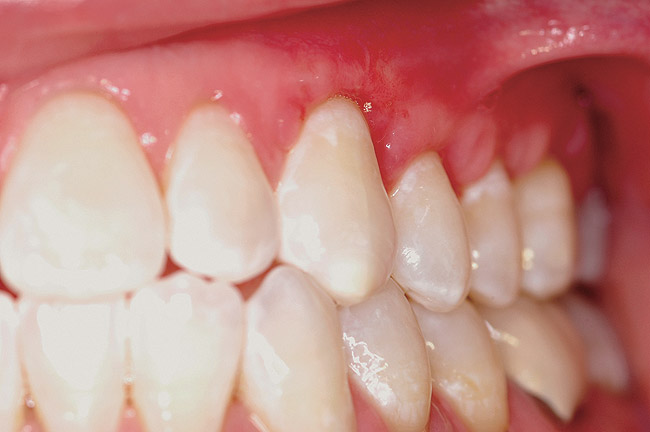

This patient presented with moderate gingival recession and minimal existing attached keratinized tissue (Figure 12). The patient’s chief complaint was discomfort when brushing. A subepithelial connective tissue allograft was placed to create a zone of attached connective tissue and achieve considerable coverage of the previously exposed root surfaces (Figure 13).

Figure 12  Moderate gingival recession present on the maxillary left cuspid and first premolar.

Figure 12

Figure 13  Recession repair on the maxillary cuspid and premolar shown 6 weeks postsurgery.

Figure 13